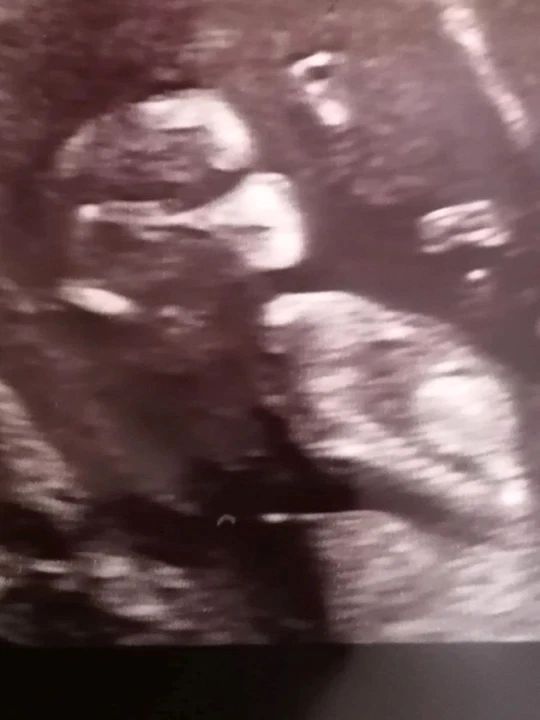

Młoda mama nie mogła powstrzymać się od śmiechu podczas badania USG. Dziecko wyglądało jakby miało na sobie maseczkę

Samantha Spicer z Northamptonshire podczas badań prenatalnych zauważyła dziwny kształt przy twarzy malucha. Kobieta od razu zaczęła się śmiać. Zdjęcie z USG wyglądało tak, jakby jej nienarodzone dziecko już miało na sobie maseczkę.

Jednak ta mama nie mogła powstrzymać śmiechu, kiedy zobaczyła na badaniu USG w 12. tygodniu ciąży, że jej dziecko jest już przygotowane na przyjście na ten dziwny świat, zanim jeszcze opuściło macicę.

Samantha Spicer dojrzała, jak cienie na badaniu ultrasonograficznym układają się w specyficzny kształt. Nos, usta i podbródek dziecka były wyraźnie jaśniejsze od reszty ciała, a ten sam jaśniejszy kolor stworzył prostą linię z tyłu głowy dziecka. Mama i personel od razu skojarzyli kształt z maseczką.

"Było to tak wyraźnie widać - powiedziała Samanta. – Lekarka spojrzała na monitor, a potem na mnie i obie zaczęłyśmy się śmiać".